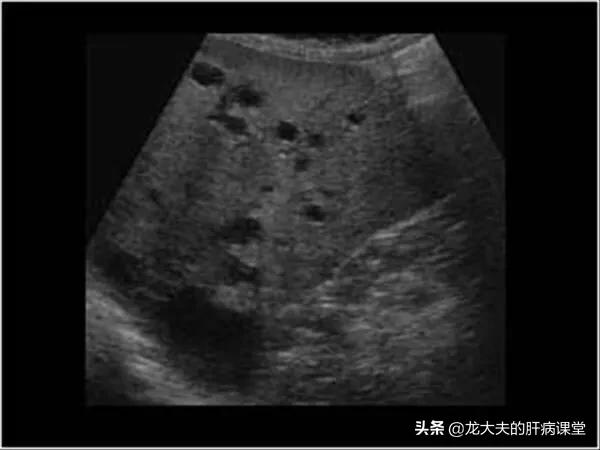

L'examen de la fonction hépatique est généralement normal, l'examen échographique de la zone hépatique peut révéler plus d'un liquide de sécurité. La tomodensitométrie ou la scintigraphie nucléaire peuvent également vérifier la présence de kystes hépatiques multiples, en plus de déterminer que les kystes hépatiques multiples n'ont pas de lésions substantielles.